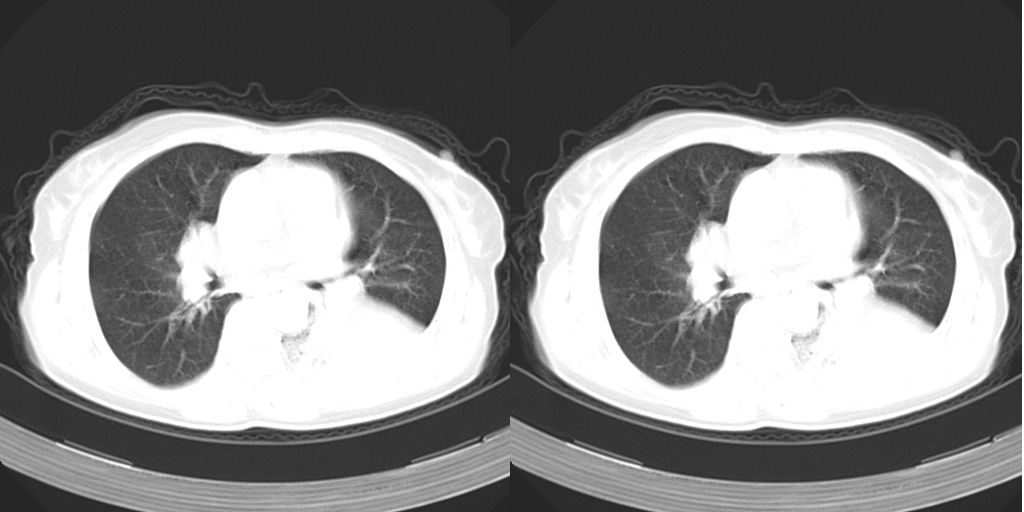

以下是引用dyqct在2007-1-23 15:01:00的发言:[br]左肺下叶实变、略萎陷,近肺门下部密度不均。上腔静脉后及隆突前见肿大淋巴结。余未见异常。[br]考虑:1、左肺下叶中心型肺癌伴肺不张、纵隔淋巴结转移;[br] 2、建议增强扫描并做任意平面重建确定肿块范围及支气管受累情况。

以下是引用dyqct在2007-1-23 15:01:00的发言:[br]左肺下叶实变、略萎陷,近肺门下部密度不均。上腔静脉后及隆突前淋巴结太多了,左下叶气管边窄、截断。余未见异常。[br]考虑:1、左肺下叶中心型肺癌伴肺不张、纵隔淋巴结转移;[br] 2、建议增强扫描并做任意平面重建确定肿块范围及支气管受累情况。

以下是引用同在2007-1-23 19:59:00的发言:[br]左肺下叶中央型肺癌伴肺不张及纵隔淋巴结转移.